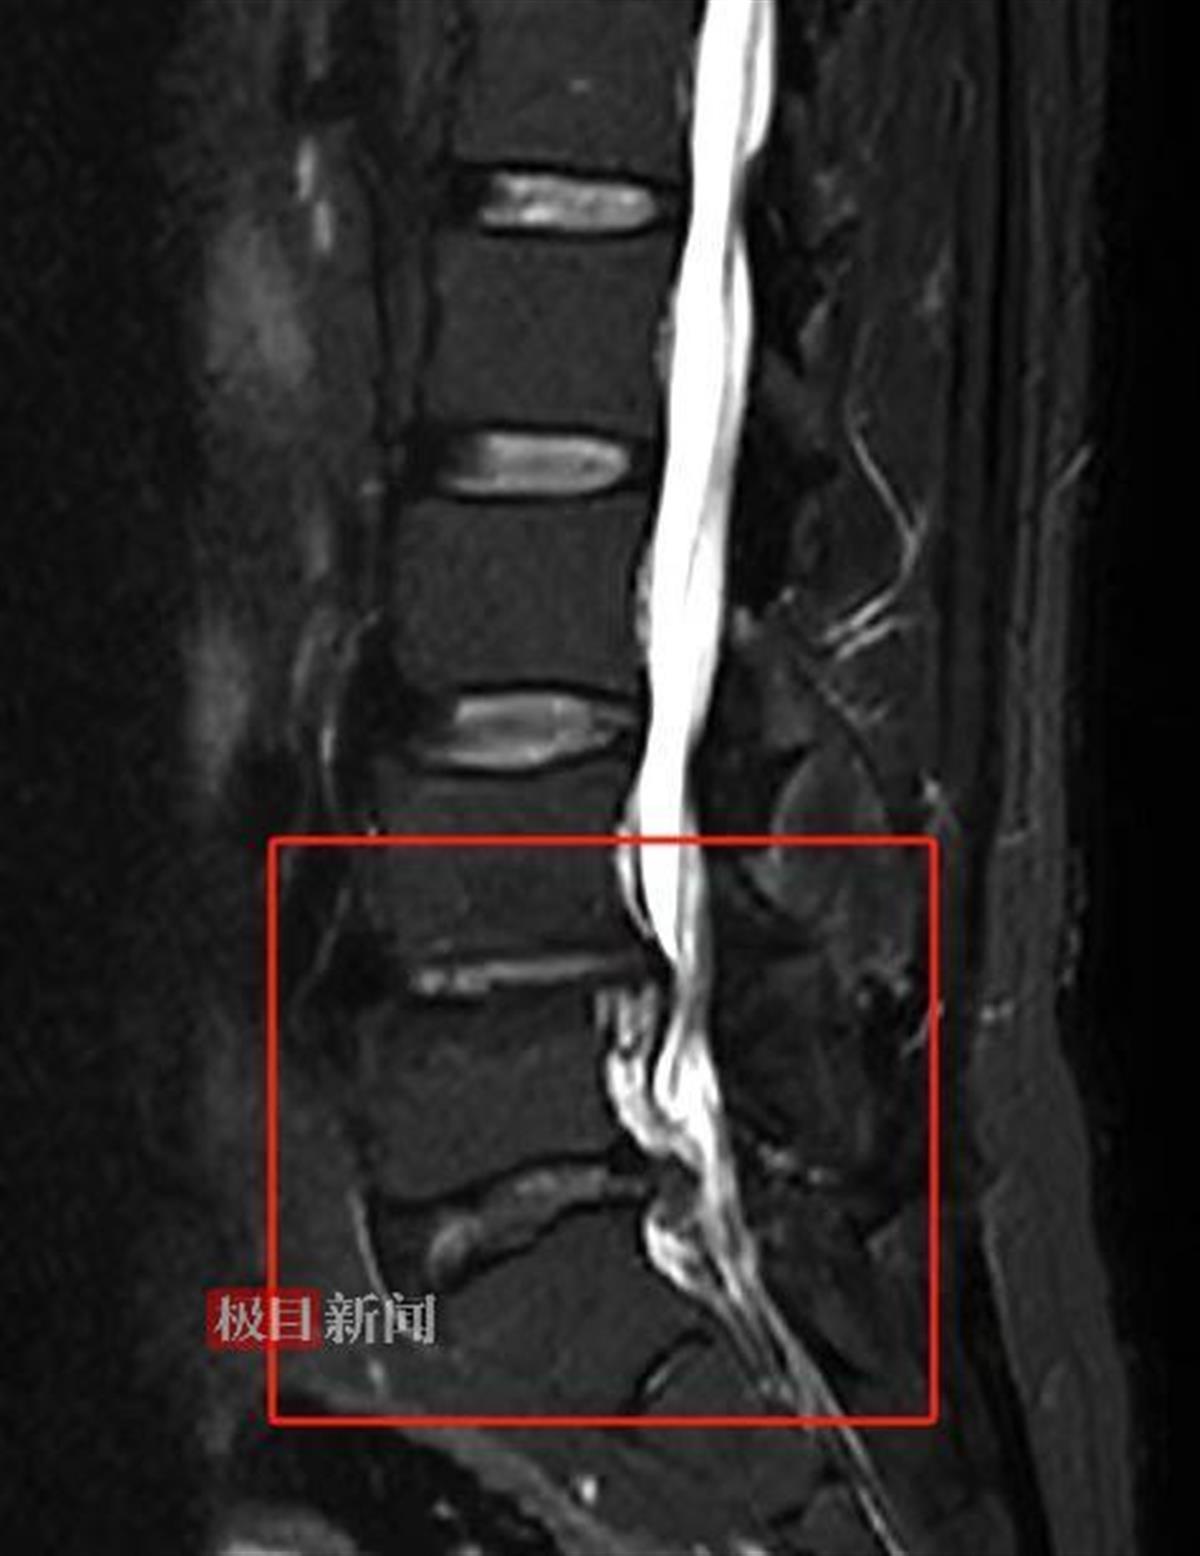

核磁共振可见患者椎间盘脱出、椎管狭窄、脊髓神经严重受压

“患者的腰椎状况颇为复杂,其中尤以椎间盘脱出、椎管狭窄导致脊髓神经受压这一状况最为严重,除此之外,还存在骨质增生、终板炎、椎间盘变性等多种异常表现。因为腰椎椎管狭窄以及椎间盘脱出等问题,已经导致了马尾神经受压,影响下肢的感觉、运动功能,如果不及时通过手术解除这种压迫,神经功能可能会进一步受损,甚至出现不可逆的伤害,严重影响患者日后的生活质量,最终导致大小便失禁、下肢永久性瘫痪等严重后果。面对如此棘手的病情,为了避免出现更糟糕的情况,患者需尽快进行手术治疗。”武汉市普仁医院脊柱骨科主治医师余双奇解释道。